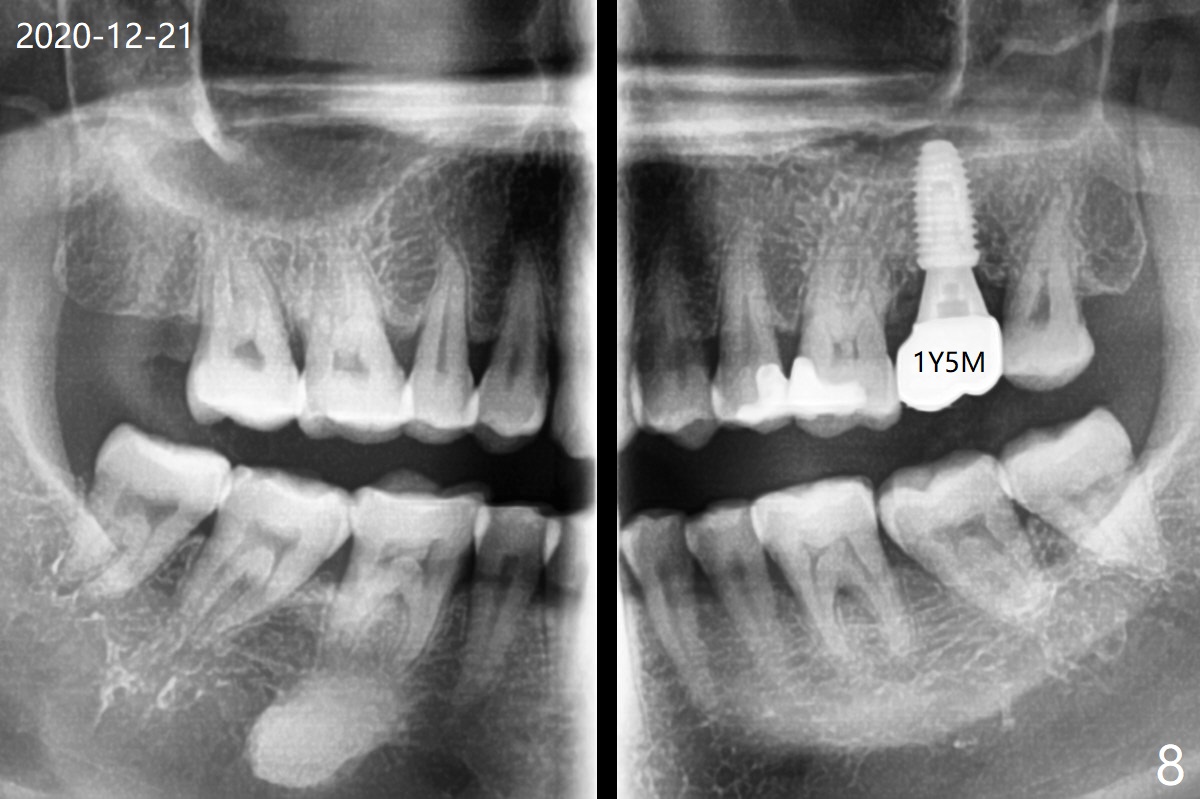

No threads are exposed 1 year 5 months post cementation (Fig.8).